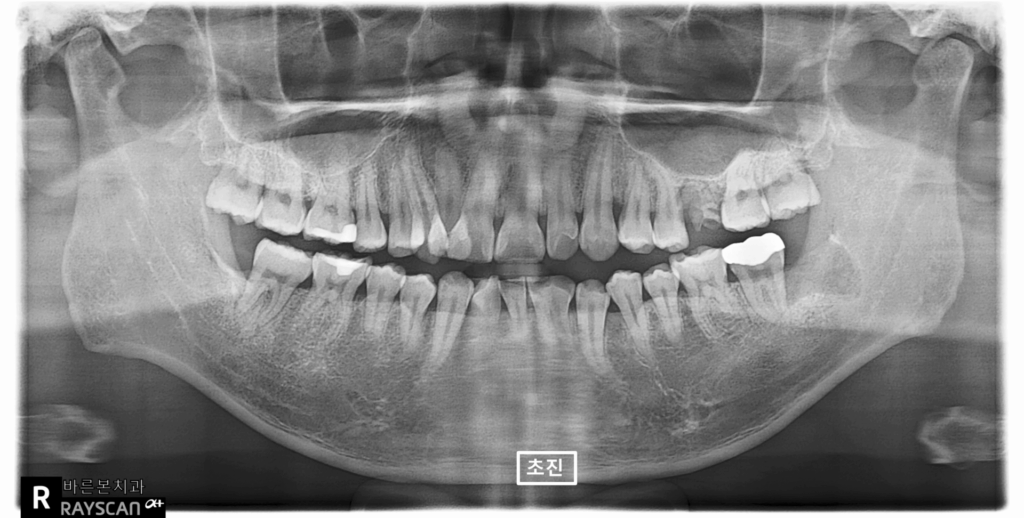

24.02.02(초진) – 34y 조OO님

” 입술물집이 생긴지 좀 됬어요.

커졌다 작아졌다 했는데 요즘은 좀

줄어든거 같아요 ” 라고 말씀하시며

매교역치과 바른본치과의원으로 내원하신

환자분의 x-ray 사진입니다.

부러진 치아도 보이네요.